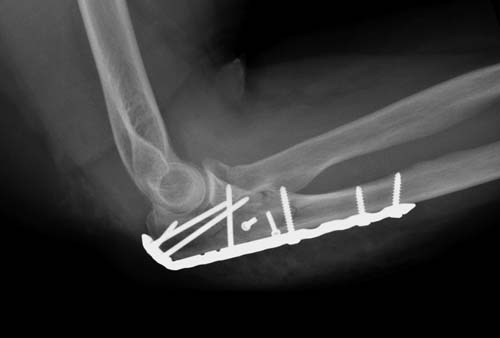

Здесь представлены несколько случаев и как видно больше больных с серьезными повреждениями, чем изолированные..

В первом случае перелом Монтеджи, где доперационно сделано оценка положения головки к остальным элементам под рентгеном. Учитывая правильность взаимотношении произведена фиксация только локтевого отростка, Второй случай, заменена на протез, и третий, кроме фиксации головки - реконструкция capitellum латерального мыщелка.